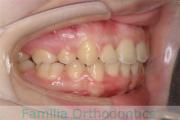

上の前歯の並びが気になるのできれいにしたい、ということで来院されました。マウスピース型矯正装置のひとつ、インビザライン/InvisalignR(薬機法および医薬品副作用被害救済制度の対象外)を用いて治療しました。

非抜歯で2年弱、20回程度の通院で治療が完了しました。

マウスピース矯正は、患者さんの協力に治療結果が左右されるところはリスクと言えるかもしれません。